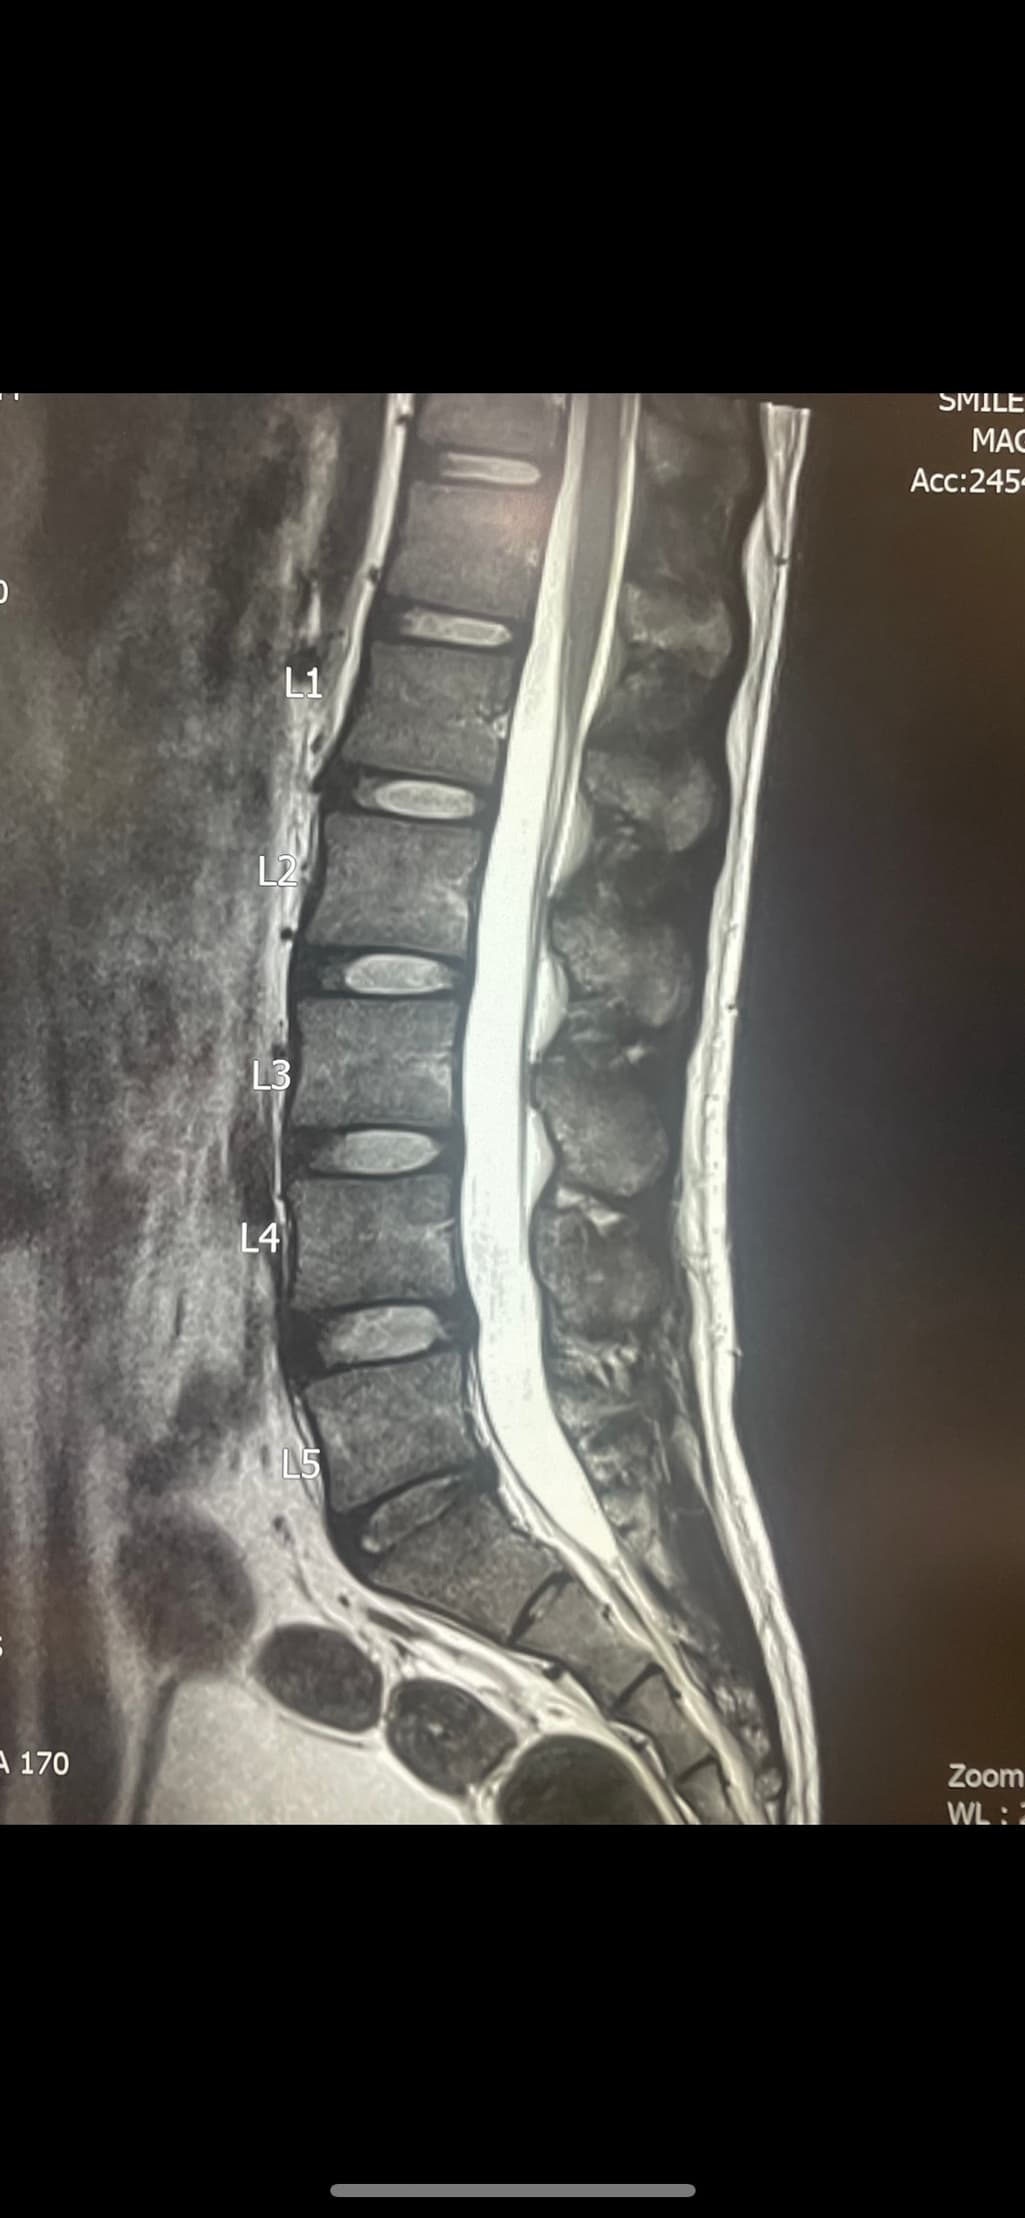

요추 5번 천추 1번 사이에 디스크내장증이 있어보입니다.

흔히 이야기하시는 디스크는 디스크탈출을 의미하는데 수핵이 탈출한 정도의 디스크는 아니고 디스크 섬유륜 일부층이 찢어지는 디스크내장증이 있는 상태로 보입니다.

디스크 내장증을 그냥 이해하기 쉬우시라고 디스크 초기라고 표현하시는 경우도 있겠습니다.

이런 상태에서 허리 관리는 매우 간단합니다. 통증이 잇는 상태라면 허리를 절대 굽히지 않는 요추전만 자세를 하루 24시간 유지하시면 되고 통증이 다 좋아지시고 나면 척추를 잡아줄 복근, 척추기립근, 광배근, 둔근 근력운동을 허리를 굽히지 않는 동작으로 해주시면 됩니다.

찢어진 디스크 섬유륜은 다시 붙을 수 있습니다. 하지만 완전히 이전같은 조직으로 돌아오지는 않고 흉터조직으로 낫기 때문에 앞으로 계속 자세를 관리하셔야겠습니다. 흉터조직은 기존의 섬유륜조직보다 다시 찢어지기 쉽기 때문입니다.

수핵은 한번 탈출해서 줄어들면 다시 그 양이 돌아오지는 않습니다. 하지만, 작성자분의 상태는 수핵이 탈출한건 없어보입니다.